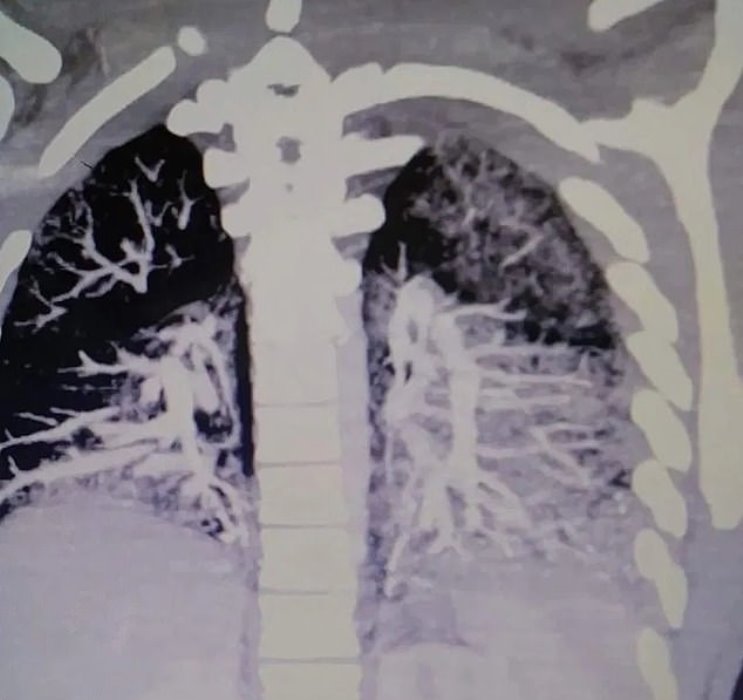

Scans revealed how vaping left his lungs filled with solidified oil that rendered him unable to breathe independently.

Doctors were shocked to discover his lungs were severely blocked with solidified vape oil, which they compared to hardened grease from frying bacon.

The condition had caused the teen, who has vaped for two years, to have ‘the lungs of a 60-year-old, 2-pack-a-day, smoker.’

Keith continued: “As the doctor says, anytime you put moisture into your lungs its not good. It’s solidified. It’s caking everything inside of his lungs.”

Anthony’s mother, Tanya, also wrote: “A warning for those in denial. This is what vaping looks like when your otherwise healthy 19-year-old is admitted into the ICU.

“Left lung [is] about 80 per cent congested and right is about 50 per cent, oxygen level was 37.

“According to the doctor this is showing areas that have essentially solidified like bacon grease.

“The pulmonary doctor said he had seen dead people with a higher oxygen level. A full recovery is uncertain… Only time will tell.”